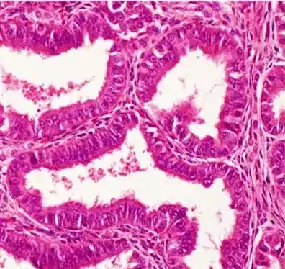

| Histopathology of a well-differentiated endometrioid adenocarcinoma in the ovary | |